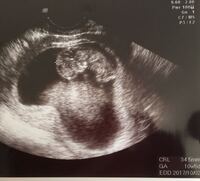

週 0 妊娠8週~11週は胎児の個体差が少なく、このときのCRL(頭臀長)(とうでんちょう)赤ちゃんの頭からおしりまでの長さから出産予定日を計算します。ただ、正確といっても±1週間の差があります。 心音が聞こえ始めます。 64 1 65 2 66 3 67 4 68 5妊娠10週目 妊娠10週目の赤ちゃんの成長 おなかの中の赤ちゃんは、わずか数週間でさらに大きな成長を遂げます。 小さな頭が丸くなってよりヒトの形に近づいてきます。 そしてママが妊娠10週目に入るころには、内臓がほぼ完全にできて動き出すように妊娠3カ月 受精から63~69日目 胎児の大きさ 頭殿長(座高・CRL)44mm~60mm 体重は10gほど 妊娠11週(11w)が何カ月かというと、妊娠3カ月です。 反射神経も発達し、膝を曲げたり伸ばしたりしています。 これは生後に見られる歩行反射で、生まれるまでに十分時間をかけて完成されていきます。 あくびや、指しゃぶりのような動きをすることもあります。

24週1日で子宮内胎児死亡。 お腹に赤ちゃんいたんです。 21年05月24日 1211 判定日後からは胎嚢が小さいとか胎芽が小さいとかめっちゃ気にしてました。 心拍確認して胎芽の時点で週数より小さくてめっちゃ心配で、無事に安定期に行くまでトツキトオカ妊娠11週(妊娠3ヶ月)エコー写真・超音波写真 妊娠11週目:受精から63~69日目・妊娠3ヶ月 胎児の大きさ:頭殿長(座高・CRL)が44~60mm 胎児の体重:10gほど この作業に時間がかかると、赤ちゃんは酸欠状態に陥ってしまう。 ギリギリだったが、なんとか成功した。 これで呼吸の管理は出来る。この時の赤ちゃんの体重はわずか261g。 日本国内で最も低体重で生まれた赤ちゃんだった。(※17年2月時点)

妊娠11週 0 2日 のエコー写真 体験談